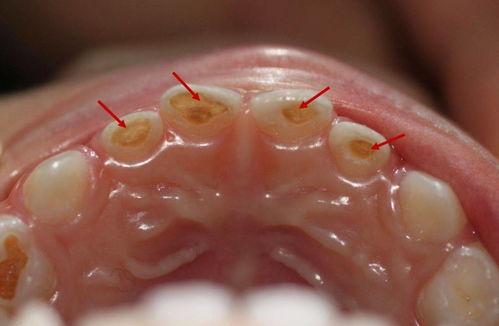

雖然輕微齲齒的齲洞可能較小,但仔細檢查仍可發(fā)現(xiàn)。這些齲洞通常位于牙齒的窩溝點隙、鄰面或牙頸部等容易積存食物殘渣和細菌的部位。

齲洞的深度較淺,一般未累及牙本質深層。

輕微齲齒的判斷標準